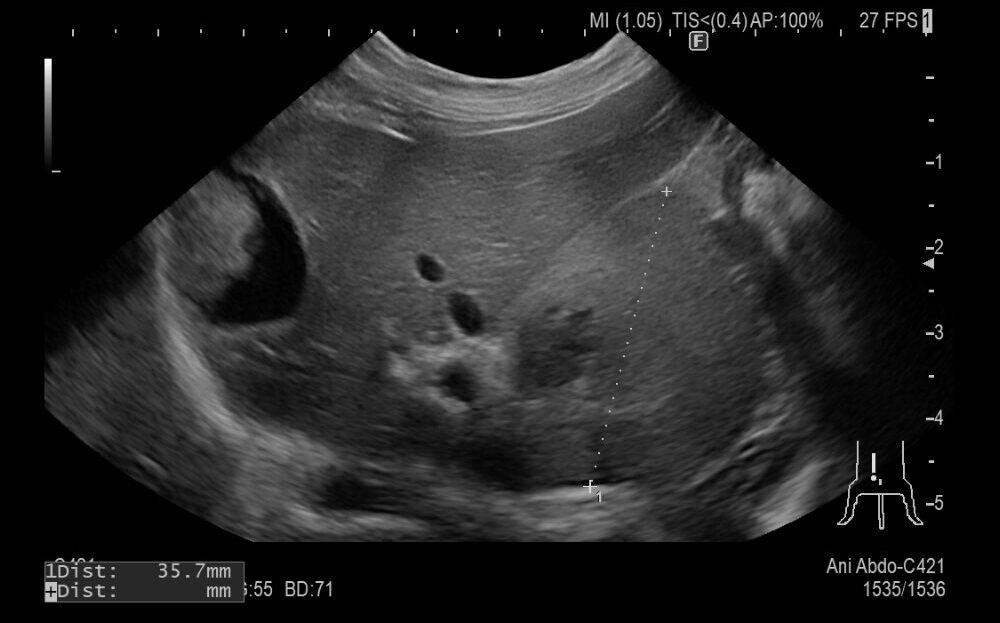

症例は9歳の柴犬でかかりつけにて肝臓に腫瘍が見つかったが、手術が難しいとのことで来院されました。

超音波で確認すると肝臓の基部に腫瘍が認められました。犬の肝臓腫瘍は肝細胞癌の可能性が高いので、摘出を行いました。